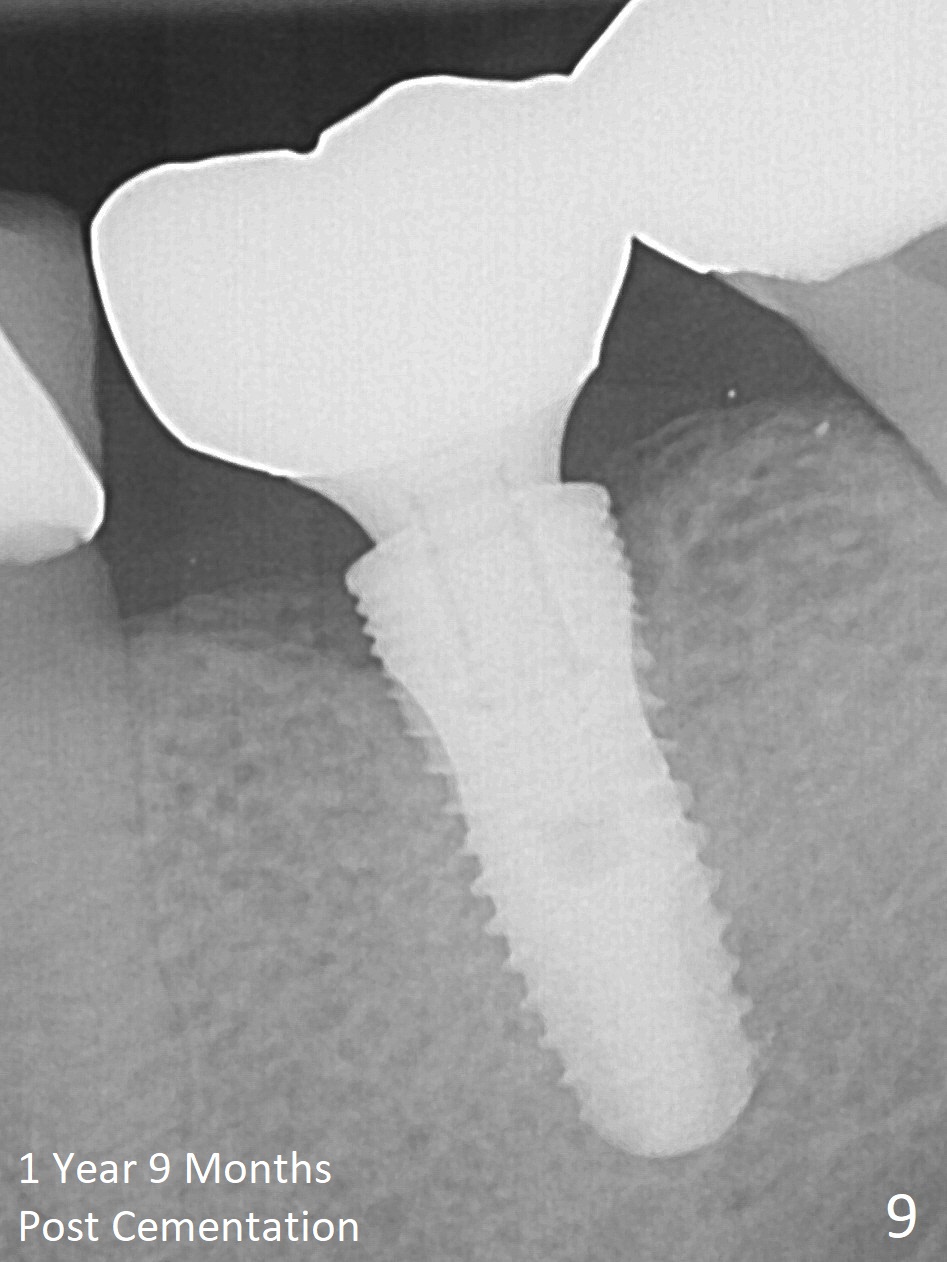

In fact, the buccal plate and the septum are defective. Osteotomy is initiated lingual to the center of the common sockets (Fig.1); depth is about 4 mm. When a 5x12 mm bone-level implant is placed (Fig.4), there is a gap mesiobuccally, which is later filled with bone graft (Fig.5 *). A large abutment (7.8x4(3) mm) is placed immediately (Fig.5 A) for an immediate provisional to close the sockets. The buccal abutment margin is ~ 1 mm subgingival, whereas the lingual ~2 mm supragingival. The abutment may need to be changed in the restorative phase (Fig.9,10).

Two months post impression (4 months postop), the patient returns for cementation. The provisional is perforated again in the occlusal surface (Fig.7 P). When the provisional is removed, a shallow trough forms around the abutment (Fig.8*). The bony defect appears to be repaired 1 year 9 months post cementation (Fig.9).